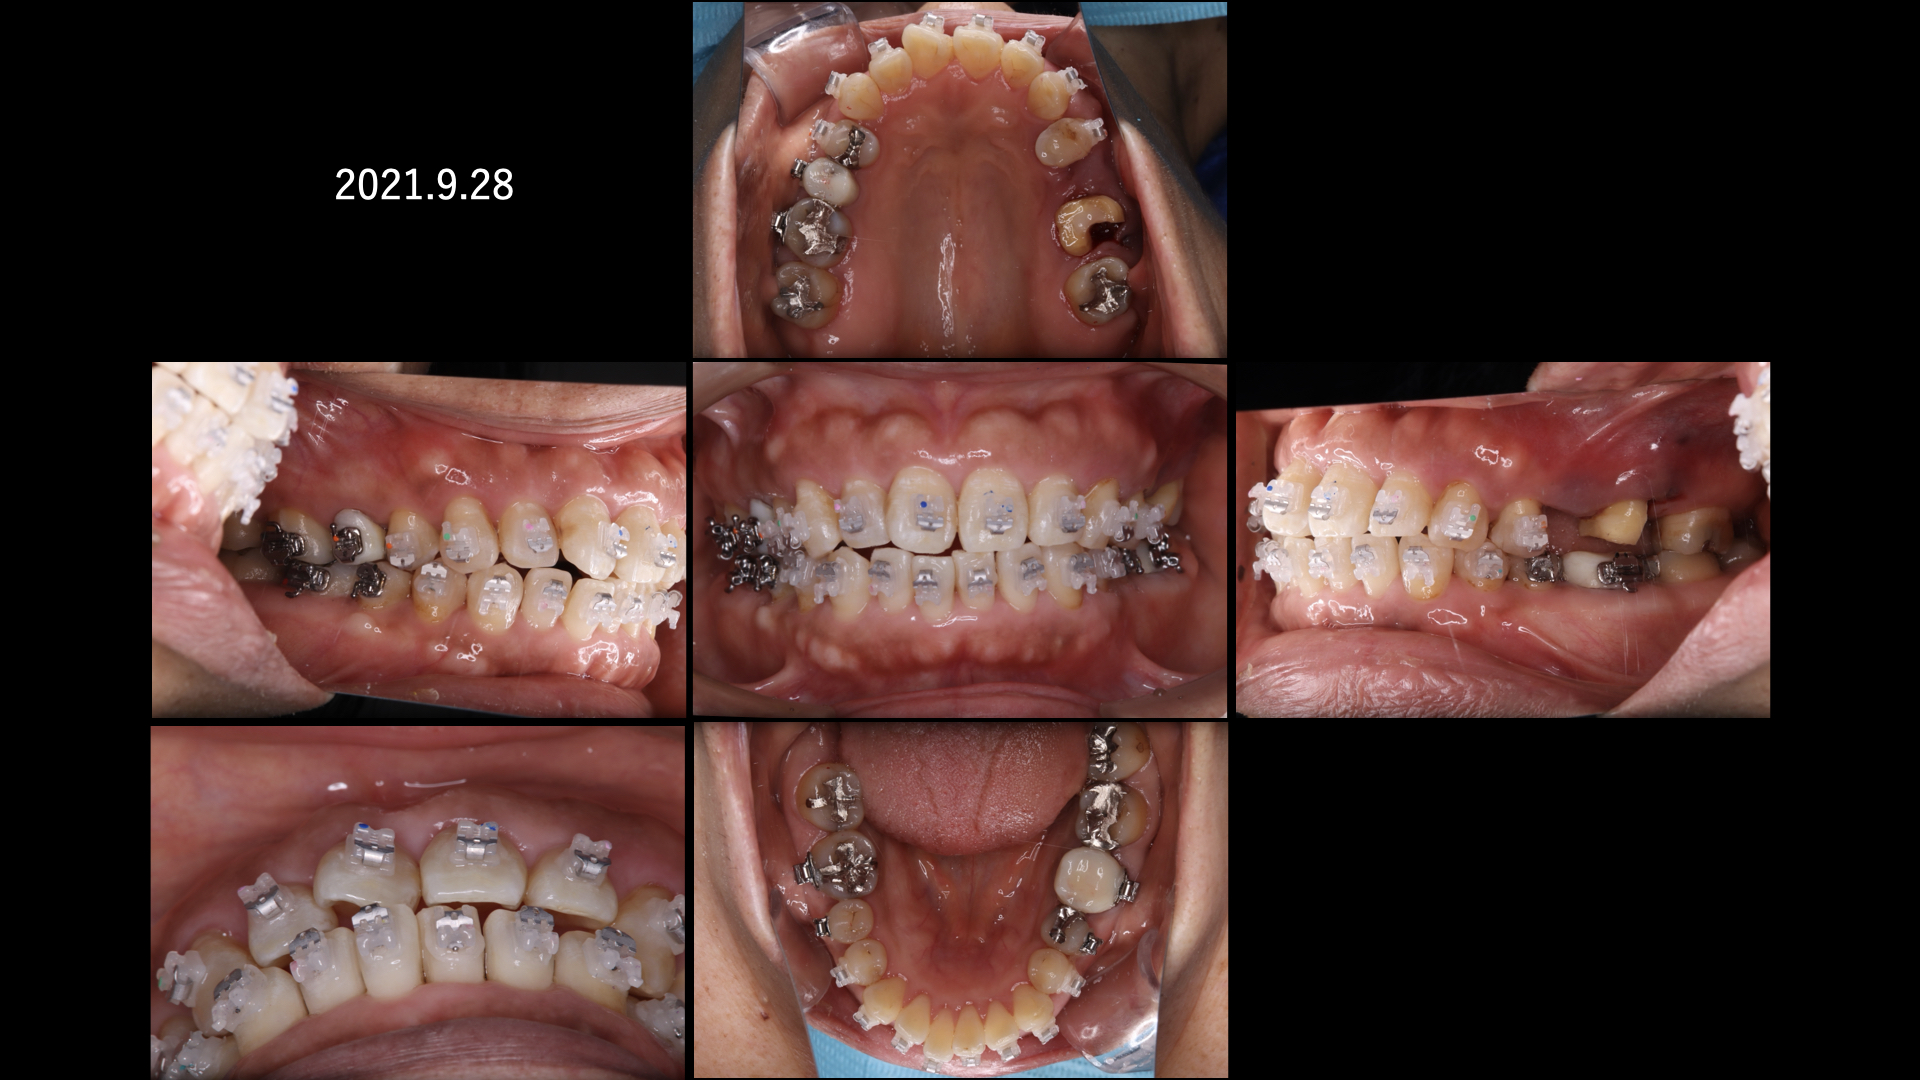

まずは奥から2番目の歯も保存を希望されましたが、治りが悪かったので一度抜歯して歯石を取り、戻してみて保存を試みました。

その間矯正治療をおこないました。

残念ながら、奥歯は腫れが引かず抜歯になってしまいました。

矯正が終わり、左上のインプラント治療に入ります。